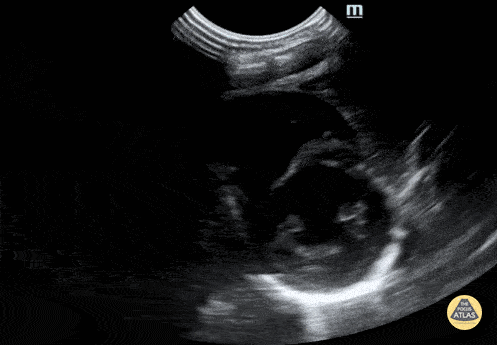

Normal PSSA in a neonate. Contributor: Jaron Smith, MD, Phoenix Children's Hospital

https://www.thepocusatlas.com/pedscardiac